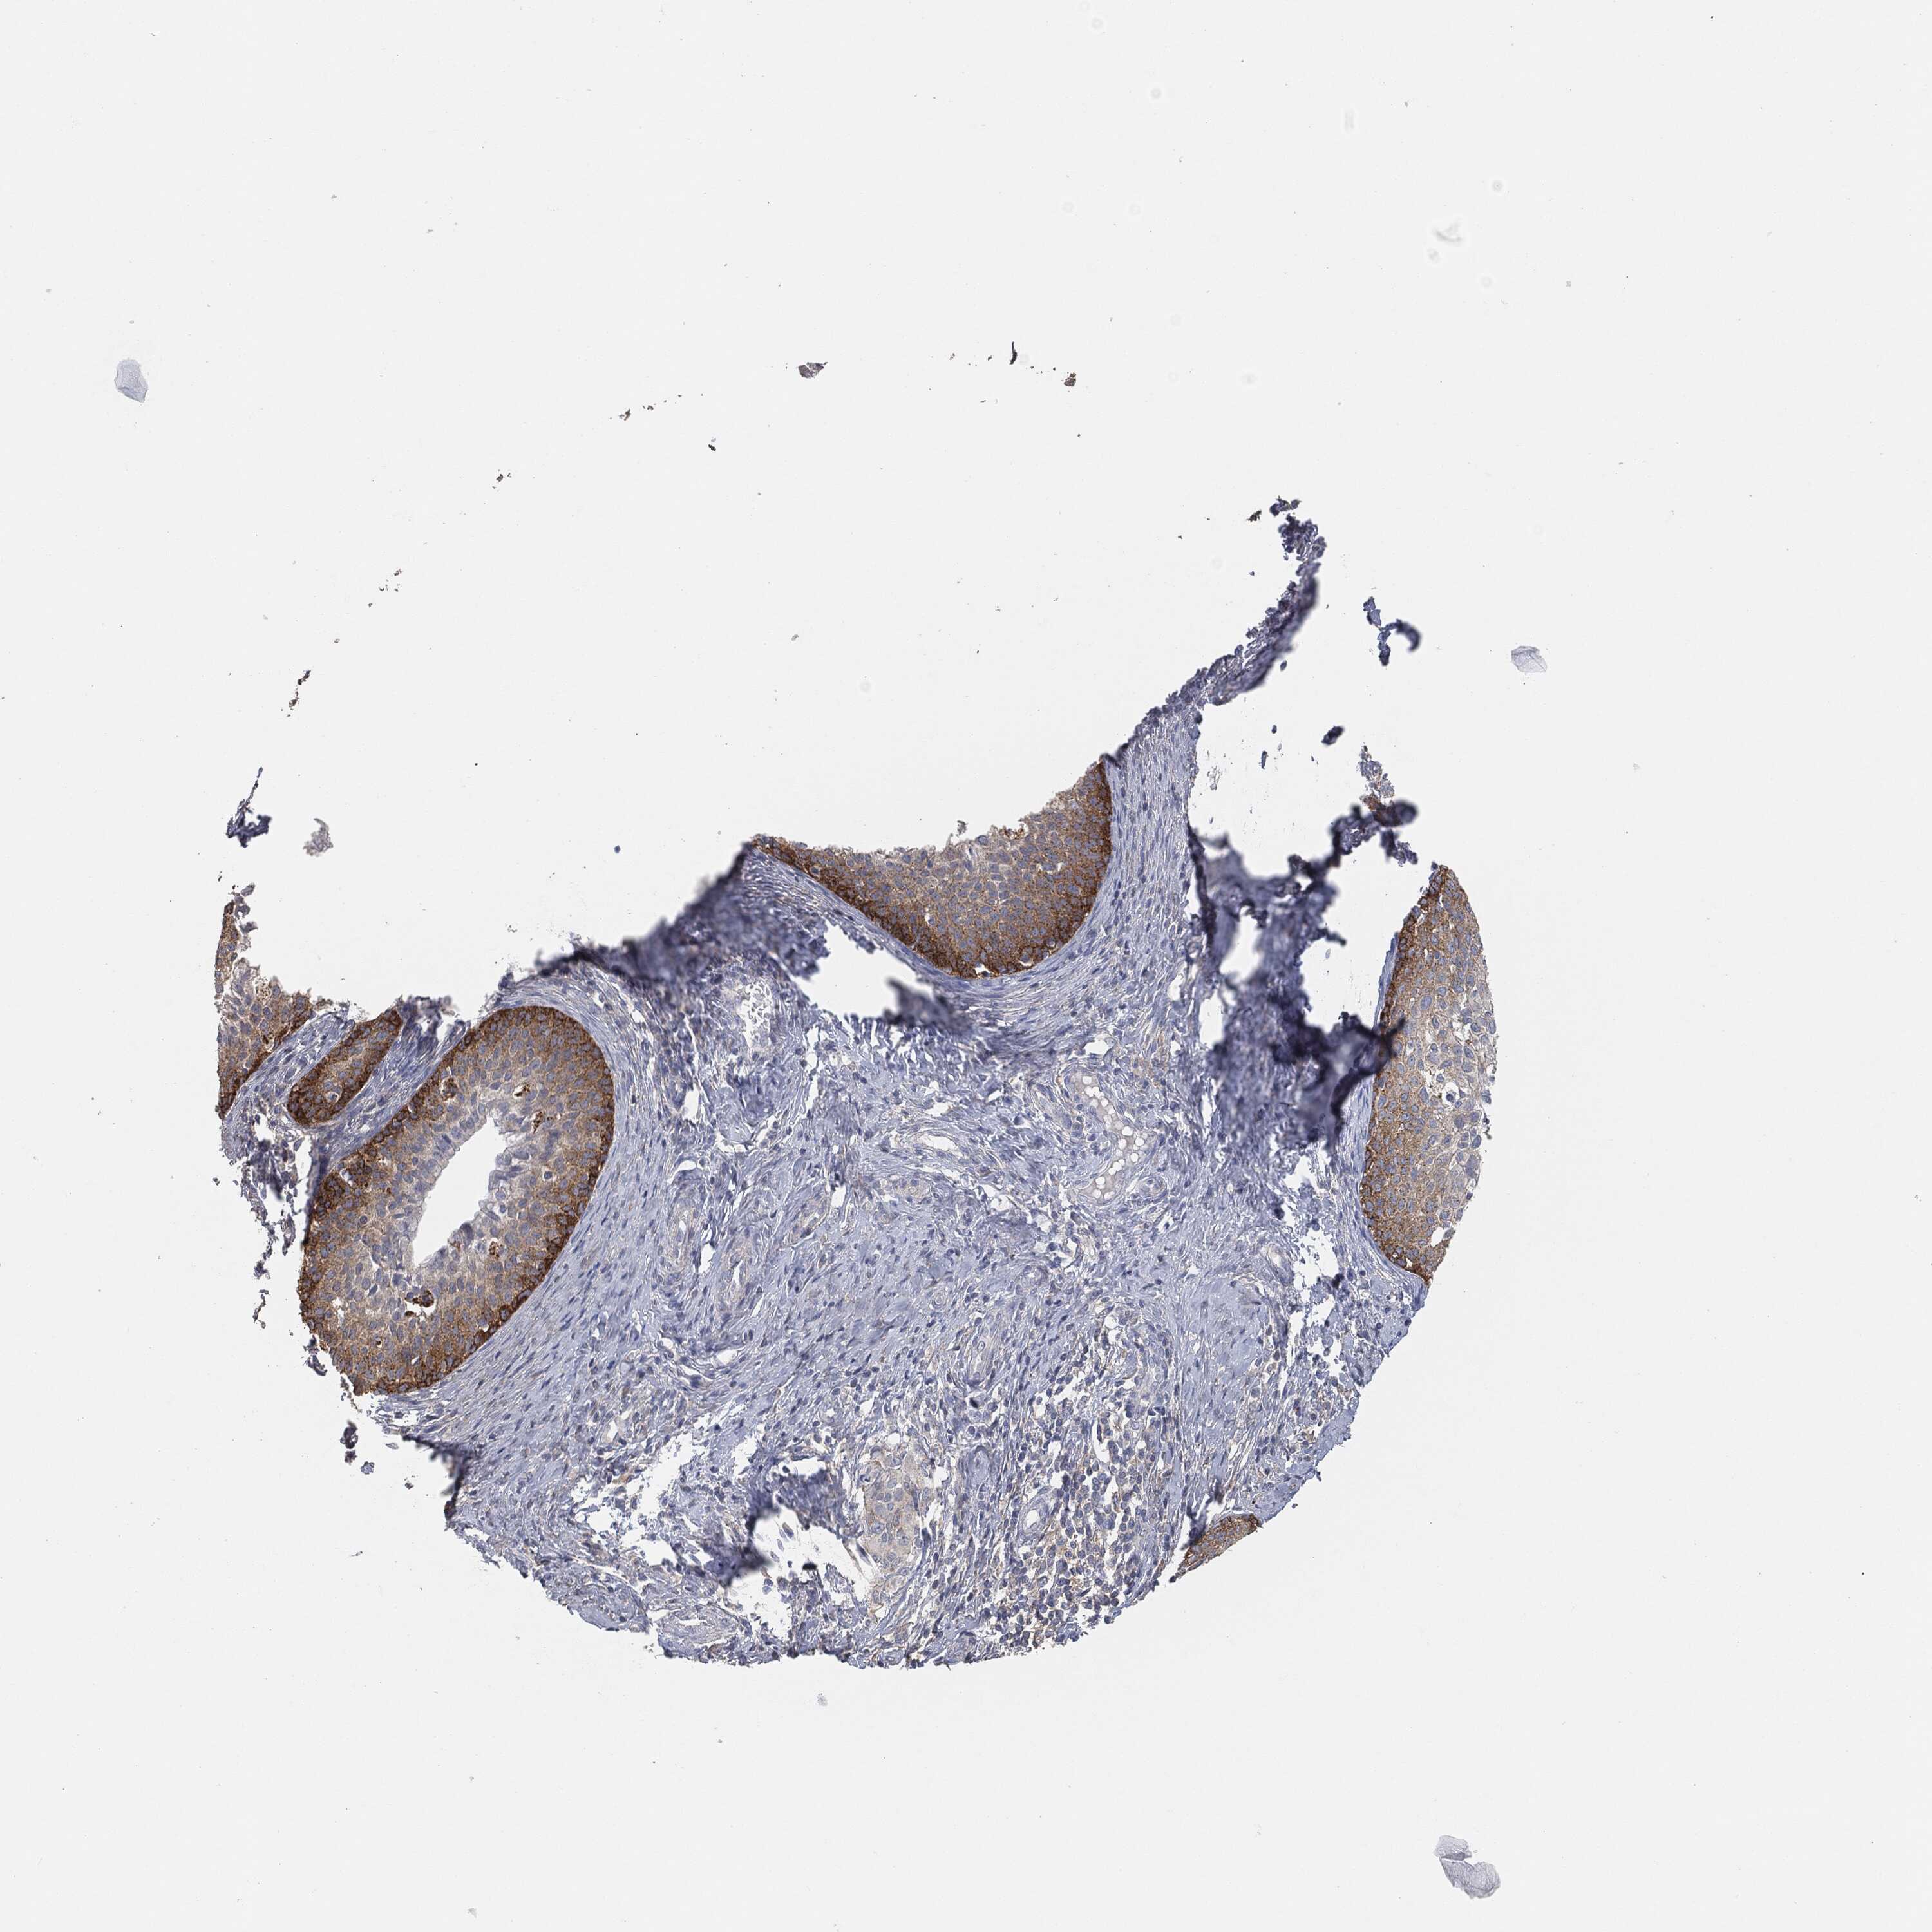

CERVICAL CANCER - Protein expressioni

A mouse-over function shows sample information and annotation data. Click on an image to view it in a full screen mode. Samples can be filtered based on level of antibody staining by selecting one or several of the following categories: high, medium, low and not detected. The assay and annotation is described here.

Note that samples used for immunohistochemistry by the Human Protein Atlas do not correspond to samples in the TCGA dataset.

Antibody stainingi

Antibody staining in the annotated cell types in the current human tissue is reported as not detected, low, medium, or high, based on conventional immunohistochemistry profiling in selected tissues. This score is based on the combination of the staining intensity and fraction of stained cells.

Each image is clickable and will lead to virtual microscopy that enables deeper exploration of all samples and also displays staining intensity scores, fraction scores and subcellular localization as well as patient and tissue information for each sample.